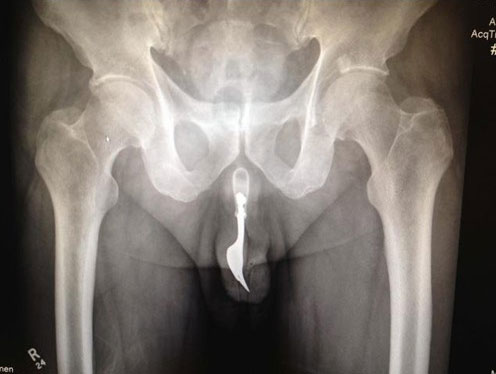

“少女怀孕”已经成为一种严重的社会危机,不仅殃及今天的家庭与社会,更是明天的夫妻与孩子,殃及整个民族的未来。少女怀孕堕胎之风几乎与避孕套推广浪潮竞相高涨。从深层的背景上看,“少女怀孕”反映着怎样的社会问题呢?

选择避孕方法,效果当然是重点考虑的问题。如今这避孕方式五花八门、层出不穷,可医院的妇科诊室依然不乏堕胎的女性,想来与避孕方法出现纰漏不无关系。那些避孕方法的失败率你可知?